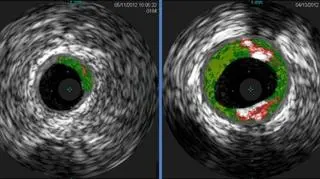

Zdjęcia ultrasonograficzne; z lewej strony niski poziom płytek miażdżycowych u osoby nieuczulonej, po prawej osoba uczulona z wyższym poziomem płytek (Angela Taylor/University of Virginia Health System)